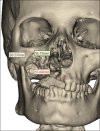

Rationale: The successful utilisation of three dimensional (3D) techniques in engineering a titanium patient specific implant (PSI) for a patient who underwent hemimaxillectomy following post COVID mucormycosis infection.

Treatment: The patient was operated for mucormycosis followed by reconstruction with patient specific implant.

Take away lessons: The advances in the use of PSI by integration of 3D printing and computer aided design computer aided manufacturing (CAD-CAM) technology for extensive and challenging defects in the maxillofacial region have been highlighted in this case report.